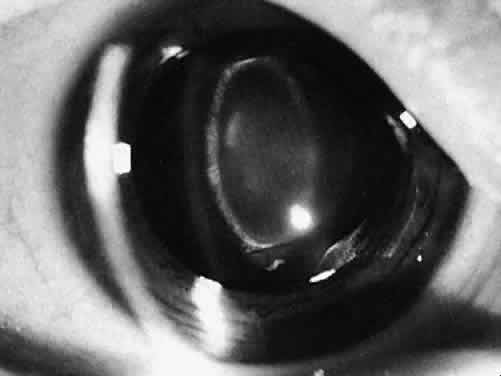

Type and Location

Usually, anterior polar cataracts are visually insignificant and allow normal visual development (see Fig. 1). However, some affect vision, and all require careful monitoring.7 Centrally located cataracts that are on or near the posterior lens capsule have a greater effect on the refraction of light and visual acuity (Fig. 2). Nuclear cataracts associated with metabolic disorders or prenatal infections produce double refracting systems that cause optical distortion and significantly decrease visual acuity (Fig. 3).

Fig. 2. A posterior subcapsular cataract that has reduced visual acuity in healthy illumination to 20/60.